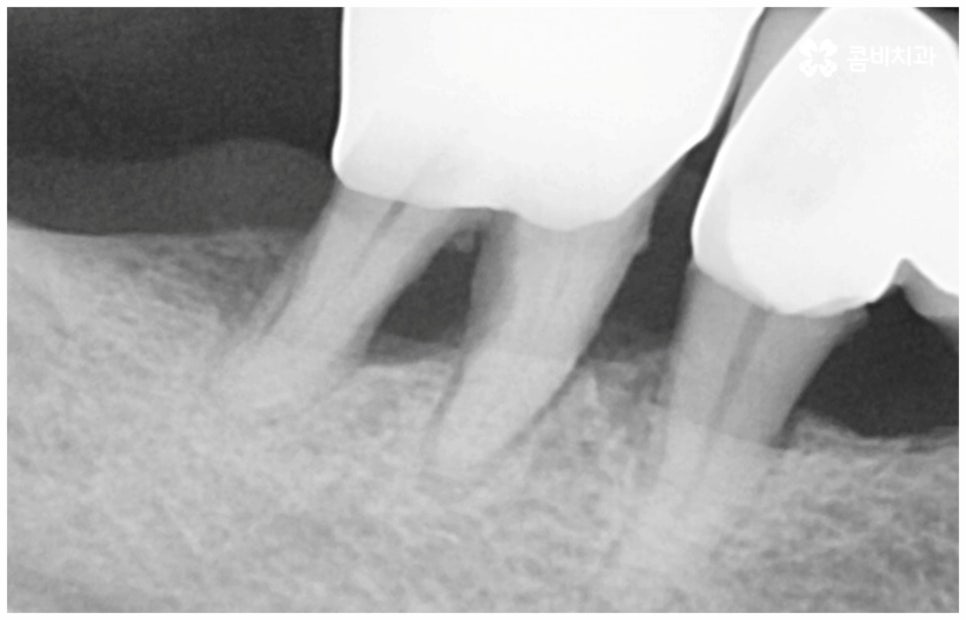

임플란트 치아에는 치아가 받는 충격을 분산시켜 주고 세균 및 외부 이물질이 침투하는 것을 막아주는 역할을 하는 치주 인대가 없기 때문에 위생 관리가 제대로 이뤄지지 않는다면 자칫 임플란트를 지지하는 잇몸에 세균이 증식하여 염증이 생기기 쉬우므로 정기 검진을 통해 임플란트 상태를 지속적으로 관찰하면서 매일의 올바른 칫솔질과 주기적인 스케일링 치료를 통해 구강 내부를 늘 청결하게 관리해 줄 필요가 있어요. 임플란트 치아 자체에는 충치가 생기지 않지만 임플란트 표면에는 치태와 치석이 쌓이기 쉬우며 여기에 증식한 세균이 주변 잇몸 내로 침투해 염증을 유발하게 되면 잇몸이 빨갛게 붓거나 피가 나고 구취가 유발될 수 있어서 주의하셔야 할 거예요. 이러한 임플란트 주위염이 심해지면 잇몸뼈까지 녹아내려 임플란트를 제거하고 재수술을 받아야 하는 경우가 생기기도 하니 철저한 사후 관리 시스템을 갖춘 치과에서 케어받으시길 권유드리고 있습니다.